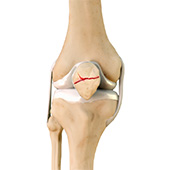

Fractures of the Patella

The patella or kneecap is a small bone present in the front of your knee where the thigh bone meets the shinbone. It provides protection to your knee and attachment to muscles in the front of the thigh. An injury to the knee can result in a break or fracture of the patella. The patella may break into two pieces or several pieces depending on the nature of the injury. Any part of the patella may be involved.

Knee Stress Fractures

Stress fractures of the patella or knee are very rare. Approximately two out of 10,000 athletes may experience a patella stress fracture. Initial symptoms include activity-related pain and then a fatigue stress fracture after minor trauma. The term insufficiency stress fracture is used for cases where the patella is weakened previously such as after patella resurfacing surgery.